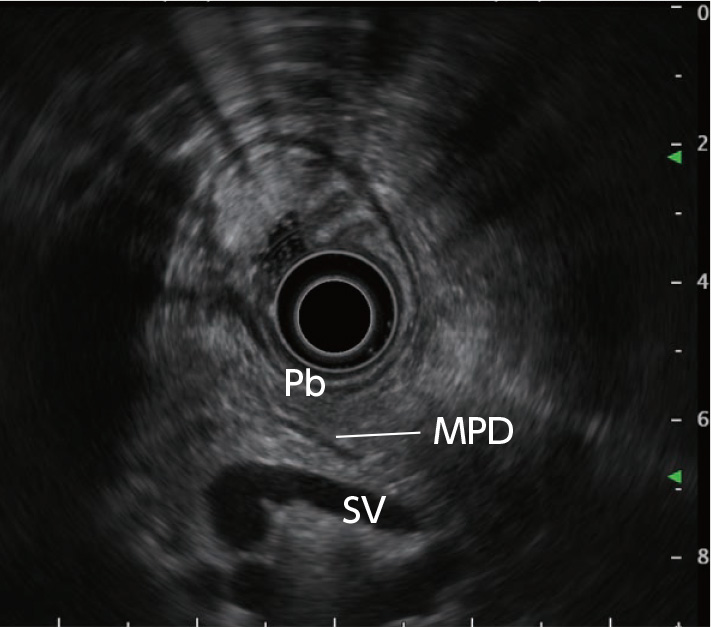

STEP 1 | Body of the pancreas

Slowly pull the scope from the gastric body or antrum to straighten the scope. Then use the splenic vein as a landmark to observe the pancreatic body.